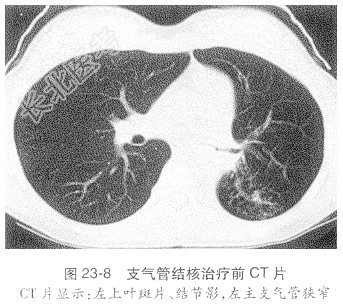

- [材料题] 患者,女性,21岁,主因“刺激性干咳2年,加重1个月”入我院。患者于2年前无明显诱因出现刺激性咳嗽,以干咳为主,偶有黄痰,诊断为“上呼吸道感染”,经抗感染治疗后咳痰好转,但仍有咳嗽。2年来反复多次出现咳嗽、咳痰加重,均经抗感染治疗后好转。入院前1个月前受凉后咳嗽加重,伴咳白痰,伴发热,体温37.5~38℃,以午后为著,经抗感染治疗后无好转,为进一步诊断治疗收入我院。入院后查胸部CT示纵隔及心脏轻度左移,右肺上叶尖后段及左上肺可见多发斑片、结节影,可见“树芽征”改变,左下肺呈肺不张影贴向脊柱旁,外缘清楚,内见少许支气管气像,左主气管及左侧各叶支气管狭窄。纵隔未见肿大的淋巴结。心脏、大血管未见异常。左侧胸腔少量积液。气管镜示气管下端左侧壁、左总、右上可见肉芽肿,表面坏死;左总远端肉芽肿表面坏死,坏死占据管腔1/2,支气管镜不能进入检查(图23-8~图23-11)。其他辅助检查:血抗结核抗体(Lam-Ab)阳性,血沉:94mm/h,痰抗酸杆菌2+,结核分枝杆菌快速培养阳性。